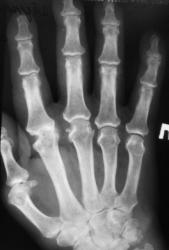

Катенёв Валенти... Дата публикации 03.07.2009, 23:53 Пациент направлен в рентгеновский кабинет "для рентгенографии кистей" терапевтом с диагнозом "Ревматоидный артрит". Произведены рентгенограммы. Ваше мнение коллеги? Сб, 04/07/2009 - 00:59 #1 Петрович Не на сайте Был на сайте: 7 лет 2 месяцев назад Зарегистрирован: 22.03.2009 - 01:13 Публикации: 3908 Для полноценной диагностики "Ревматоидного артрита" маловато представлено костей запястья. А из того, что представлено видна Подагра. Или нет? Неоднозначно всё Сб, 04/07/2009 - 12:12 #2 Ермолаев Не на сайте Был на сайте: 8 лет 10 месяцев назад Зарегистрирован: 07.02.2009 - 16:33 Публикации: 670 Соглашусь с мнением Петровича! Больше похоже на подагрический артрит. dok Вс, 05/07/2009 - 01:12 #3 OPEXOB Не на сайте Был на сайте: 9 лет 11 месяцев назад Зарегистрирован: 26.07.2008 - 10:02 Публикации: 280 Господа, мнения разделились. Поясните, кто что видит, а не окончательный диагноз. Подагра? где тофусы, "пробойники". Вс, 05/07/2009 - 12:31 #4 Ермолаев Не на сайте Был на сайте: 8 лет 10 месяцев назад Зарегистрирован: 07.02.2009 - 16:33 Публикации: 670 Коллега Орехов! Мнения, как раз и не разделились, а сошлись в одном - подагра. dok Вс, 05/07/2009 - 15:50 #5 alexey.krasnov Не на сайте Был на сайте: 10 лет 3 месяцев назад Зарегистрирован: 19.05.2009 - 10:52 Публикации: 30 Абсолютно согласен с Др. Ермолаевым и остальными. Bis Dat Qui Cito Dat

Для полноценной диагностики "Ревматоидного артрита" маловато представлено костей запястья. А из того, что представлено видна Подагра. Или нет?

Соглашусь с мнением Петровича! Больше похоже на подагрический артрит.

Господа, мнения разделились. Поясните, кто что видит, а не окончательный диагноз.

Подагра? где тофусы, "пробойники".

Коллега Орехов! Мнения, как раз и не разделились, а сошлись в одном - подагра.